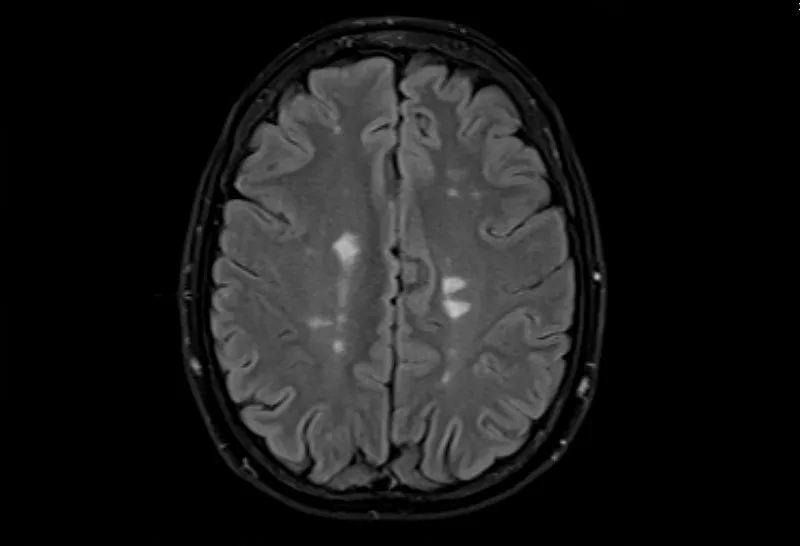

多發(fā)性腦硬化癥的磁共振成像,軸位Flair視圖

• 大腦的MRI掃描可以顯示損傷區(qū)域,但沒(méi)有單一的測(cè)試可以診斷MS。

測(cè)試的組合用于診斷MS。最好的測(cè)試是對(duì)您的大腦和脊髓進(jìn)行核磁共振檢查,以檢測(cè)損傷區(qū)域。您可能還需要進(jìn)行血液檢查、腰椎穿刺和測(cè)量神經(jīng)活動(dòng)的測(cè)試。